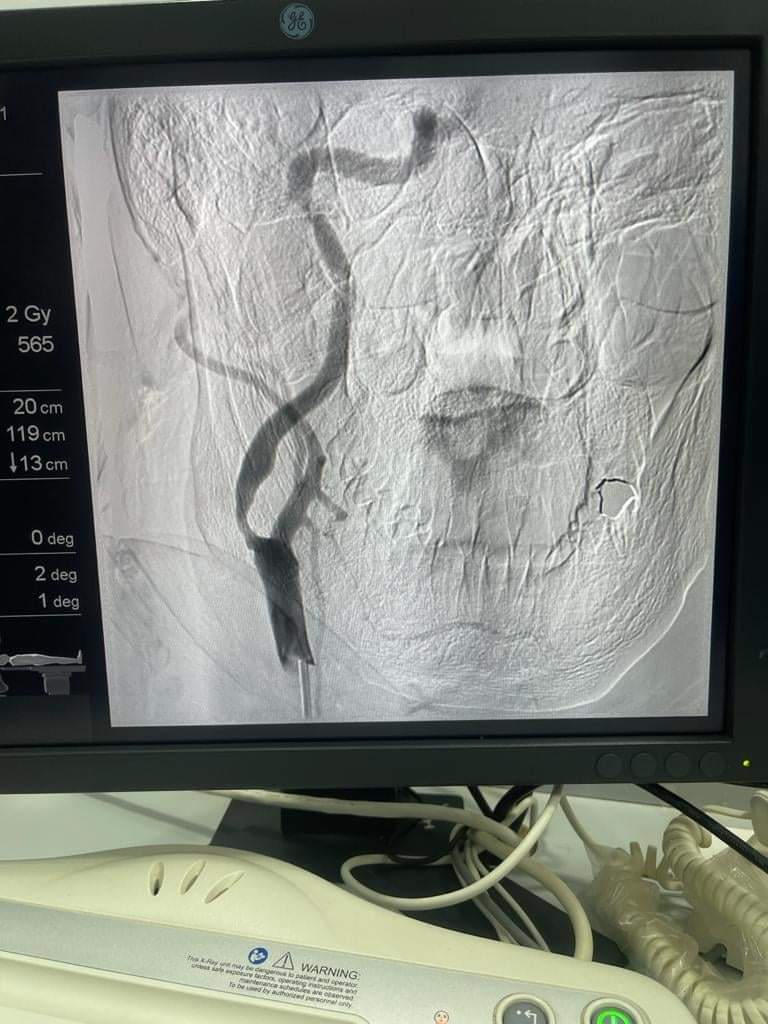

حدث جديد من نوعه، وانتصار طبي عظيم لأول مرة يَحُدث في الفيوم، بعد إجراء أول قسطرة مُخية لحالتين داخل مستشفى التأمين الصحي بالمحافظة في يوم واحد لحالة تعاني من ضيق في الشريان السُباتي، وأجرى العملية الدكتور أحمد البسيوني، أستاذ القسطرة المُخية بجامعة عين شمس، والدكتور مصطفى عبد الحفيظ، رئيس قسم المُخ والأعصاب بمستشفى الفيوم العام، ومدير وحدة السكتة الدماغية بمستشفى التأمين الصحي بالفيوم.

وتابع: “لدكتور أحمد البسيوني، أستاذ القسطرة المُخية بجامعة عين شمس، ورئيس المجلس العلمي للزمالة المصرية للمخ والأعصاب زار الفيوم، وقام بإجراء أول قسطرة مُخية لحالتين بالفيوم داخل مستشفى التأمين الصحي بالفيوم، وهو أحد أعلام القسطرة المُخية على مستوى الجمهورية والشرق الأوسط، وقام بجهد ممتاز في إجراء العملية، حيث عكف على تدريب عدد كبير من الأطباء على القسطرة المُخية حتى وصل إلى الفيوم، وتم إجراء أول قسطرة مُخية حيث جهزنا له حالتين كبداية تجريبية، الحالتين لاثنين من الرجال، حالة منهما كانت تُعاني من ضيق في الشُريان السُباتي، وأخرى مُصابة بنزيف على المخ، وتراوحت أعمارهم مابين 60 سنة، و40 سنة”.

واختتم الدكتور مصطفى عبد الحفيظ، رئيس قسم المُخ والأعصاب بمستشفى الفيوم العام، قائلا: “القسطرة المُخية، وفكرة القساطر هي الدخول في الوعاء الدموي بسلك رفيع السُمك ليبحث عن وجود خلل من الداخل لمحاولة إيجاد حلًا لها، ولها عِدة استخدامات وعلى رأس الاستخدامات إزالة الجلطة المُخية التي تكونت في وقت من 6 ساعات لـ 24 ساعة، من خلال القسطرة، والحقنة المُذيبة للجلطة المُخية وقتها 4 ساعات ونصف، فإذا حدث للمريض جلطة ووصل الطوارئ بعد مرور ساعتين أوثلاثة ساعات، من الممكن إعطائه الحُقنة، ومن المحتمل نجاح الحُقنة وتحقق نتائج جيدة، ومن الممكن أنِّ تفشل في الحصول على نتائج جيدة للمريض، فبذلك نلجأ هُنا لاختيار القسطرة المُخية، وعند مرور 4 سنوات ونصف، نلجأ أيضًا مباشرةً للقسطرة المُخية”.